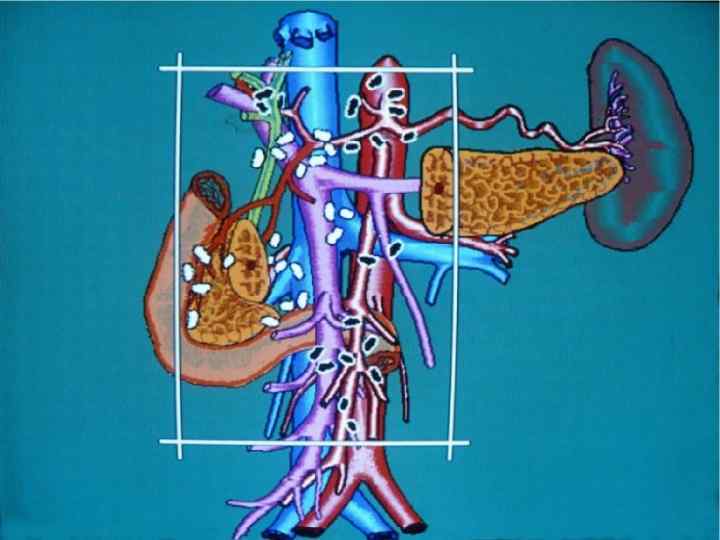

Инвазия чревного ствола и общей печеночной артерии

Резекция чревного ствола и общей печёночной артерии при выполнении ДСРПЖ Вид резекции Циркулярная резекция чревного ствола Всего Число больных с пластикой 4 без пластики 11 15

Верхняя мезентерикография после резекции чревного ствола с ушиванием обоих концов сосуда наглухо. Кровоснабжение печени осуществляется через гастродуоденальную артерию